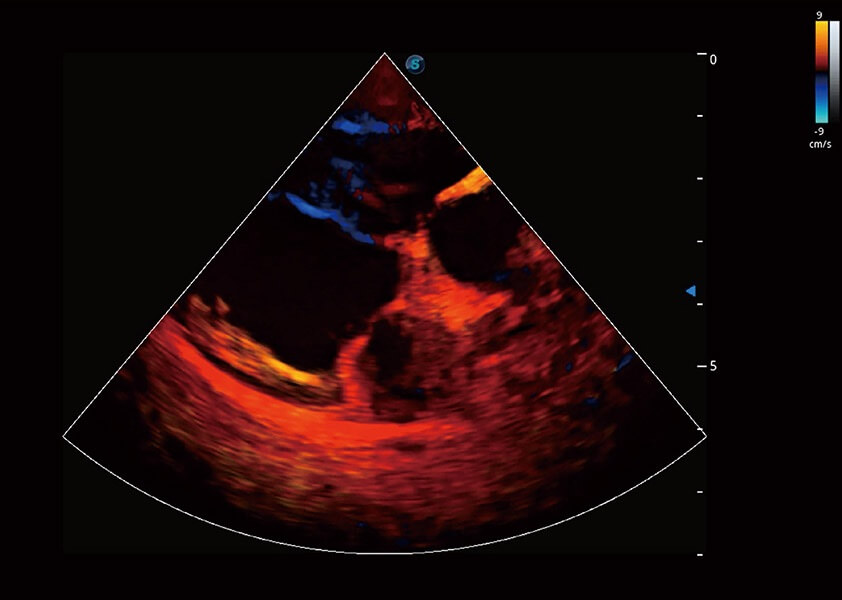

ProPet 60 作为一款高端台式动物超声设备,为动物医生的日常诊断提供了一系列贴合动物临床需求、解决临床实际问题的高级成像功能。凭借全系列高清探头,满足医生对腹部、心脏、生殖、浅表、肌骨等成像的所有需求,切实帮助您提升检查效率,提高诊断信心。

兽用彩色多普勒超声诊断系统